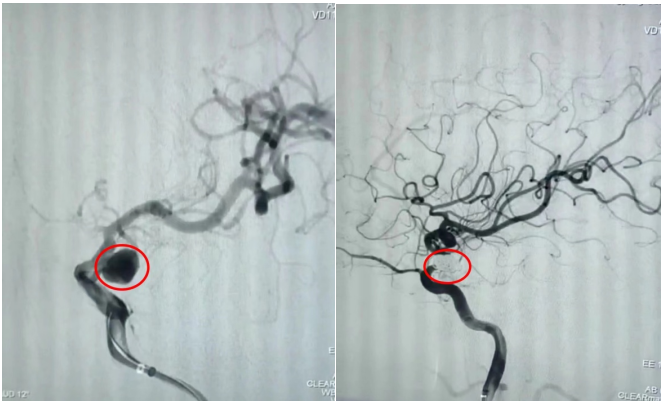

通訊員劉洋、劉立君報道: 9月2日家住衡山縣的劉爺爺從衡陽市中心醫(yī)院神經(jīng)內(nèi)科出院了。劉爺爺8月22日因左側(cè)頸內(nèi)動脈后交通段動脈瘤破裂致蛛網(wǎng)膜下腔出血,病情危在旦夕,在衡山縣人民醫(yī)院行急診全腦血管造影明確病因后,連夜轉(zhuǎn)入衡陽市中心醫(yī)院神經(jīng)內(nèi)科治療。衡陽市中心醫(yī)院神經(jīng)內(nèi)科介入團隊立即接手病人,經(jīng)過認真查看病人、細致分析病情,聯(lián)合介入室、麻醉科為病人緊急行動脈瘤介入栓塞術(shù),手術(shù)順利,術(shù)后通過腦脊液置換、預(yù)防腦動脈痙攣、預(yù)防深靜脈血栓、預(yù)防感染等綜合治療措施,緩解了劉爺爺?shù)念^痛癥狀,避免了并發(fā)癥的發(fā)生,10天后劉爺爺又回到了衡山縣人民醫(yī)院進行后續(xù)康復治療。